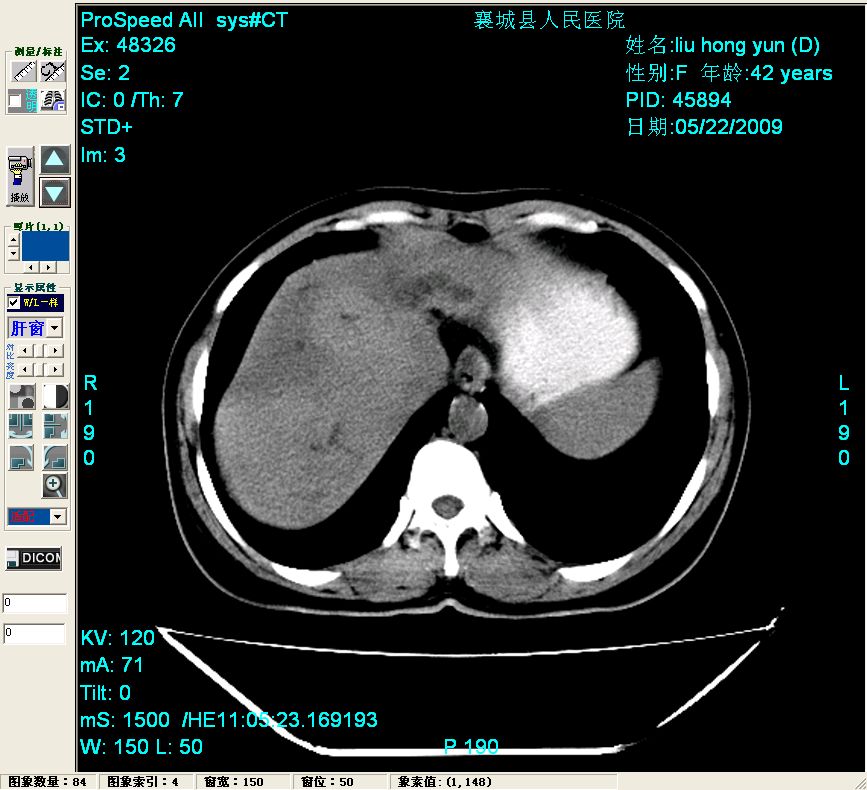

平扫:

平扫左肝外叶体积显著减小,左肝外叶见多房囊性低密度区,左肝实质及右肝前叶浅表实质呈低密度改变,左肝及右肝前叶胆管扩张,脾大

2左肝及右肝前叶表现考虑胆囊摘除术后所致的肝动门脉瘘形成,慢性纤维组织炎性增生.不完全除外左肝胆管细胞癌

脂肪肝

胆管细胞癌可能性大